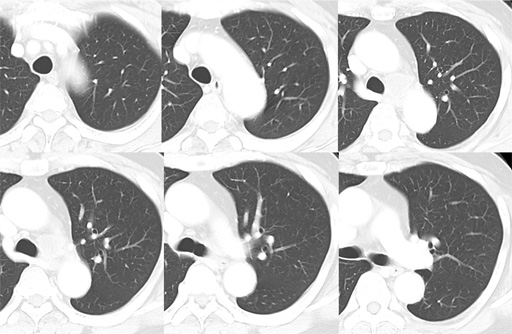

(sagittal image) 図6 胸部CT 肺野条件

図6 胸部CT 肺野条件 図7 MRI T1WI (in phase)